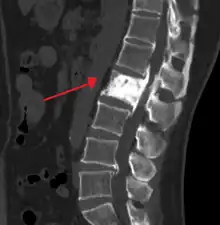

An ivory vertebra due to probable Paget disease

The first clinical manifestation of Paget's disease is usually an elevated alkaline phosphatase in the blood.[6]